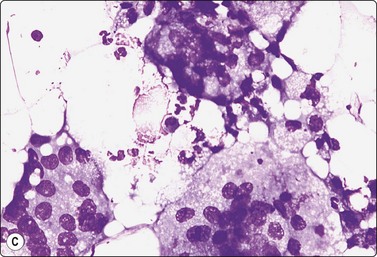

image image image

Fig. 7.19 Fat necrosis

(A) Postoperative fat necrosis. Necrotic tissue, debris and macrophages; fragment of adipose tissue upper right (MGG IP); (B) Fragments consisting of altered adipocytes, macrophages and fat droplets (MGG, IP); (C) Several multinucleated histiocytes with foamy cytoplasm (MGG, HP).

Criteria for diagnosis

A ‘dirty’ background of granular debris, fat droplets and fragments of adipose tissue,

Foamy macrophages, multinucleated giant cells and adipocytes with bubbly cytoplasm,

Chronic inflammatory cells,

Absence of epithelial cells.

Postoperative changes in response to prior surgical excision or biopsy give similar findings. Fat necrosis is always in the differential diagnosis of nodules in scars or chest wall after surgery, particularly mastectomy. Vigorous or repeated palpation of breast tissue or previous aspiration of the site can result in the same changes. The aspirate is usually scanty, sometimes of oily fluid, and consists mainly of fat with some foamy macrophages or altered, vacuolated adipocytes and multinucleated histiocytic giant cells. The untidy background of granular debris represents the actual necrosis and is the most specific diagnostic feature (Fig. 7.19A,B).

The dispersed presentation of macrophages, particularly if the cytoplasm is dense or nonvacuolated and the nuclei are large with an irregular shape and prominent nucleoli, may mimic a malignant cell pattern, particularly in air-dried MGG smears. Multinucleate forms and foamy cells with similar morphology are helpful in preventing error (Fig. 7.19C).102 Conversely, some carcinoma cells may resemble macrophages. Immunostaining or excision is sometimes necessary.